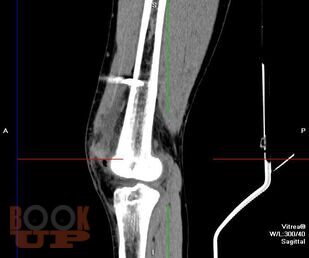

Роль мультиспиральной компьютерной томографии в комплексной клинико-лучевой диагностике острого гематогенного остеомиелита у детей

В учебно-методическом пособии представлены этиология, патогенез, клиника, осложнения, лечение, комплексная ультразвуковая, рентгенологическая, мультиспиральная компьютерная томографическая семиотика острого гематогенного остеомиелита у детей. Пособие раскрывает современные подходы ранней диагностики острого гематогенного остеомиелита у детей и предлагает оптимальный алгоритм ранней диагностики.